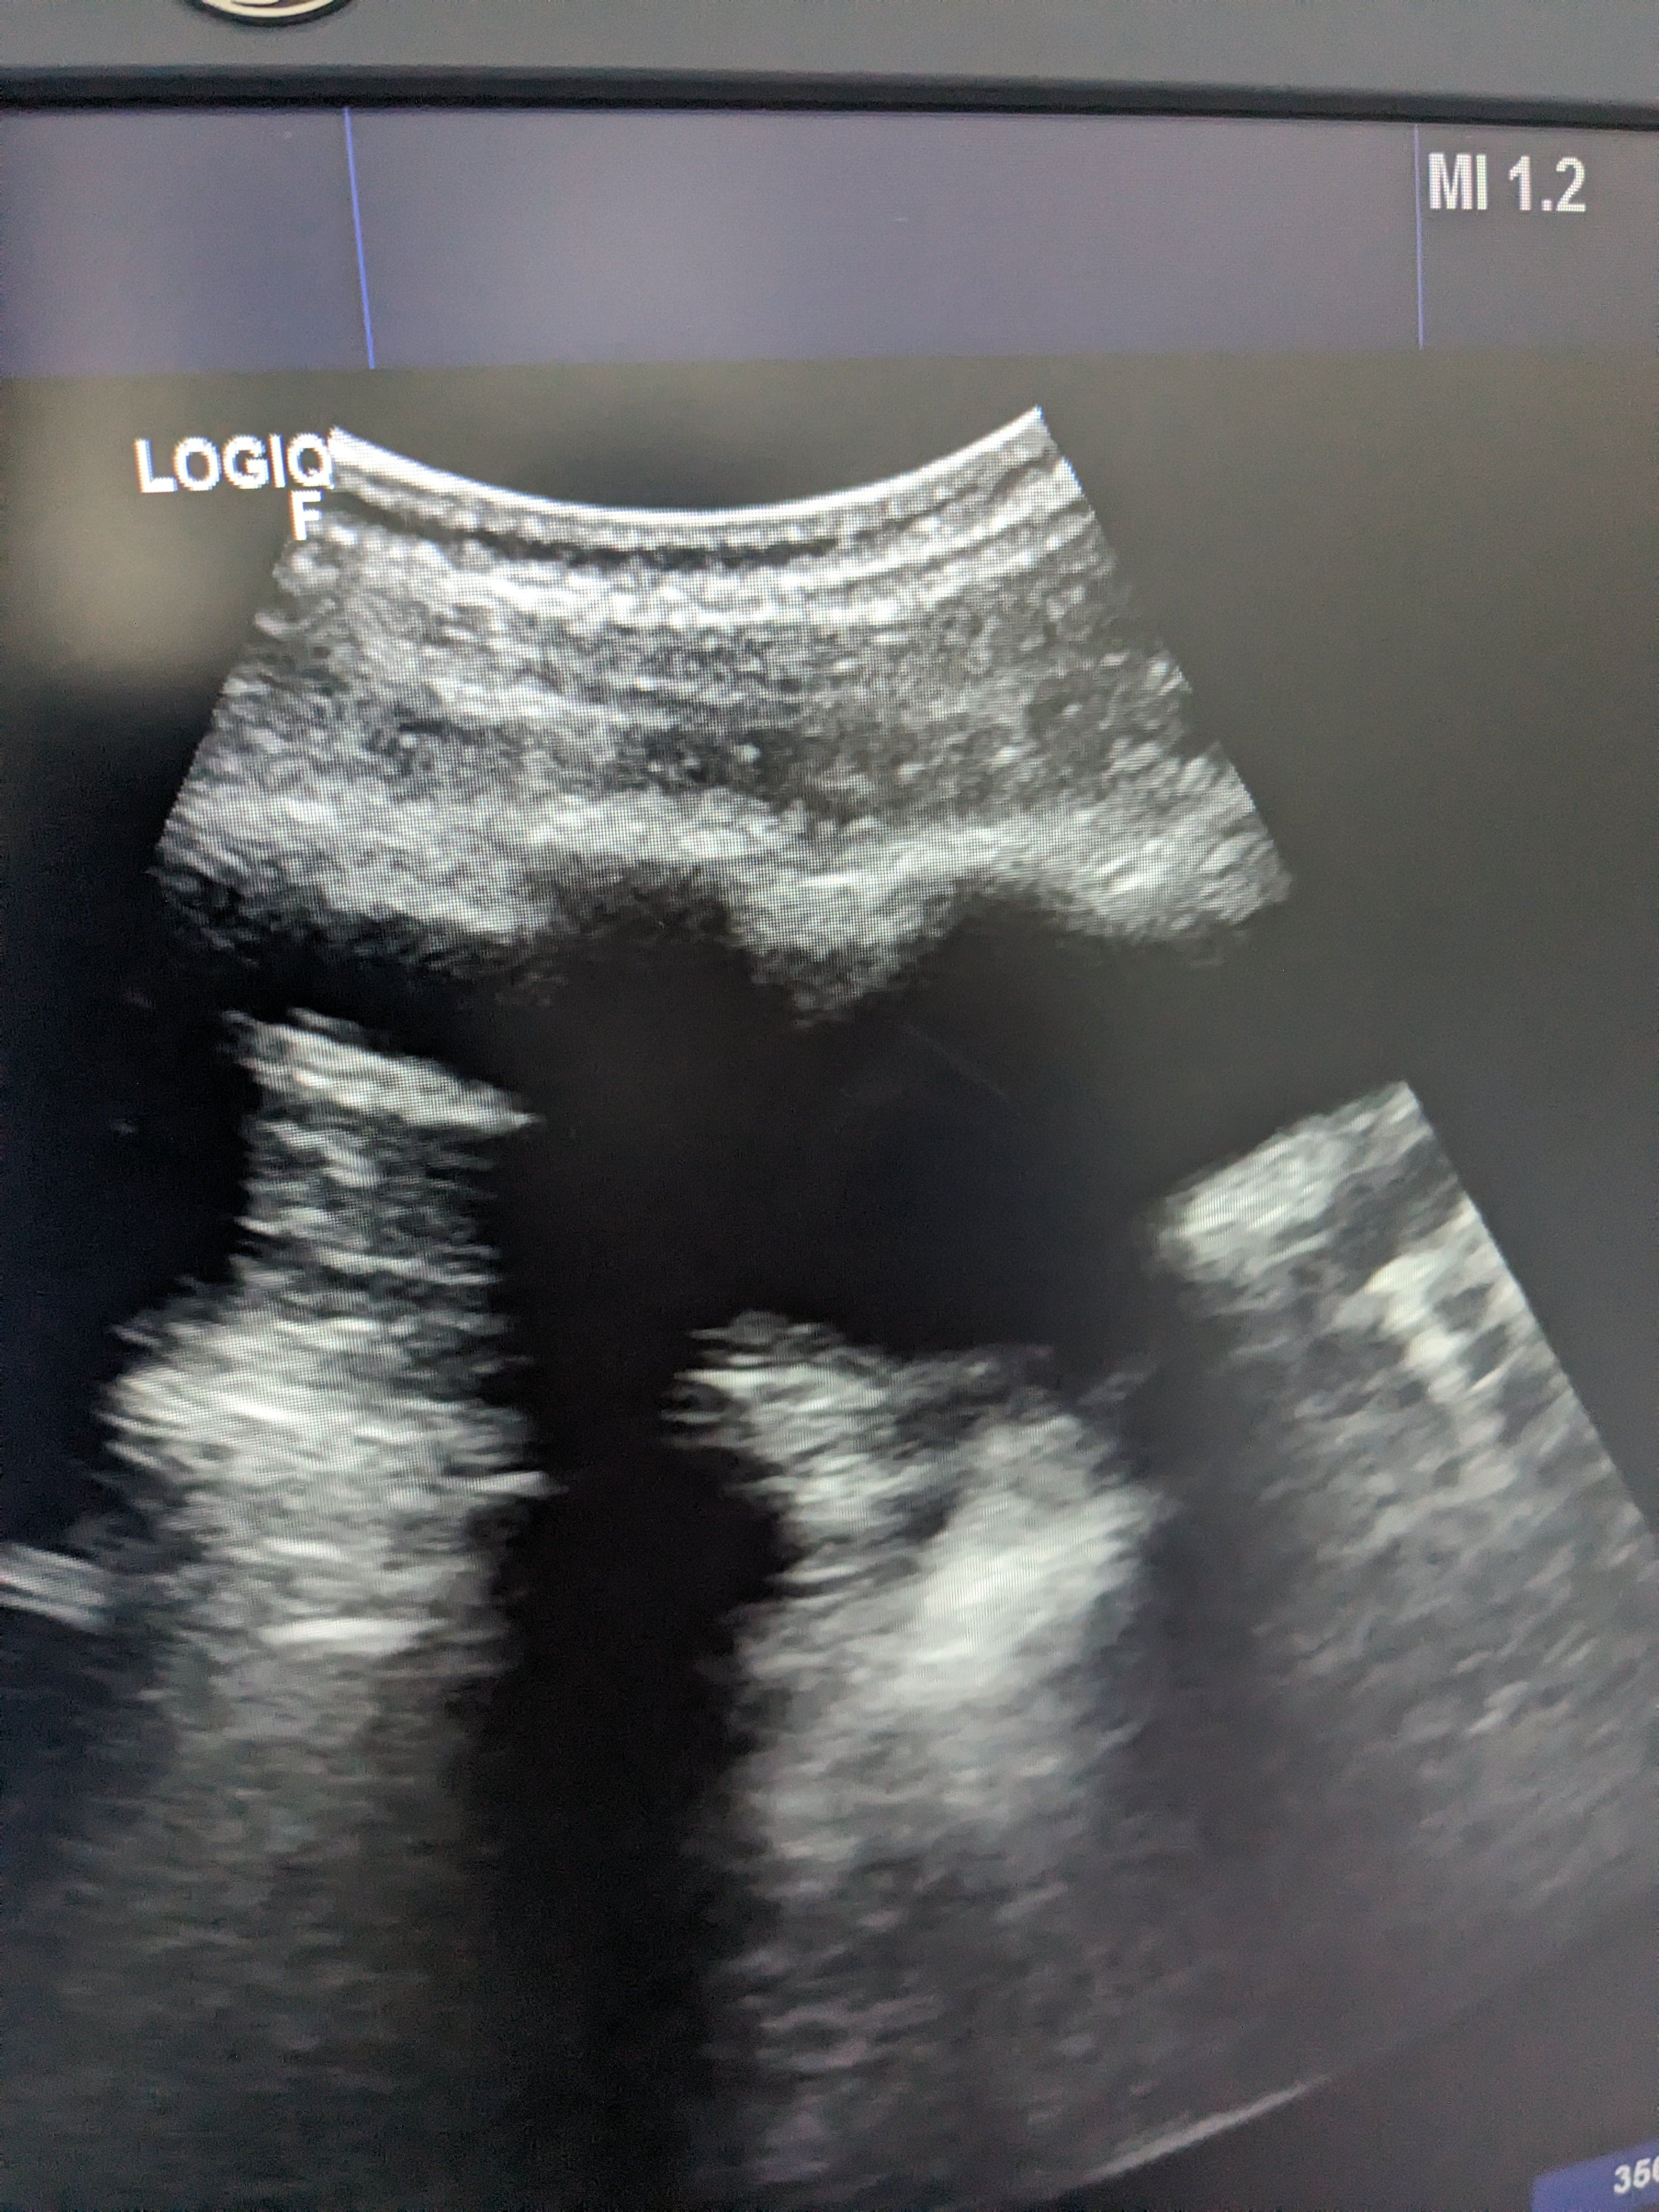

Se hace ecografía clinica en la consulta de atención primaria, observamos derrame pleural en pulmón izquierdo hasta medio campo pulmonar.

Se orienta como derrame pleural de origen desconocido por lo que se deriva a urgnecias del hospital de referencia para valoración de pruebas complementarias y tratamiento.

Rx torax: derrame pleural izquierdo. Sin pinzamiento de seno derecho. Sin infiltrados ni condensaciones.